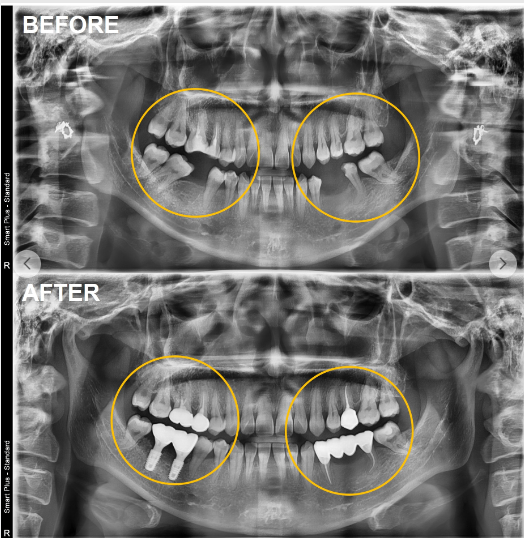

(어금니 브릿지+임플란트 치료 사례)

다음으로 중요한 것은 나와 비슷한 치료 사례가 있는지 확인하는 것입니다.

"앞니가 빠진 경우",

"어금니 여러 개가 없는 경우",

"뼈가 많이 부족한 경우" 등

자신과 유사한 상황의 치료 과정과 결과를 사진이나 영상으로 설명해주는지 살펴볼 필요가 있습니다.